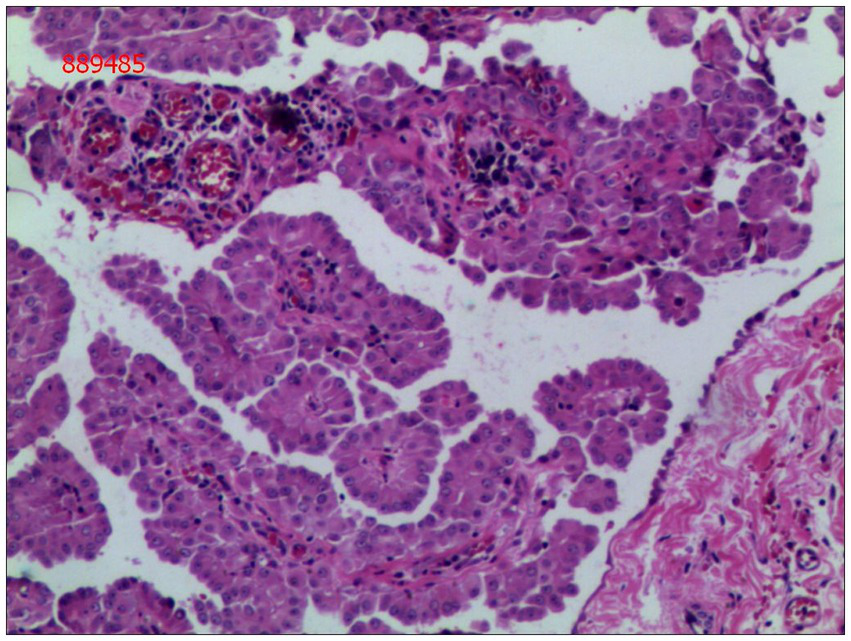

Gross examination of the resected specimen revealed a grey-white nodular mass measuring approximately 4*3*5 cm, characterized by a firm and scar-like consistency (Figure 2). Histologically, the mass extended from the submucosal layer to the serosa of the distal ileum, infiltrating and growing within the intestinal wall and adipose tissue, displaying a fascicular or woven pattern arrangement. The spindle-shaped cells exhibited abundant cytoplasm, elongated nuclei with wavy features, interspersed with collagen fibers, and minimal infiltration of inflammatory cells (Figures 3, 4).

Figure 3. The cells were spindle-shaped, with abundant cytoplasm, and interspersed with collagen matrix (hematoxylin and eosin; magnification ×40).